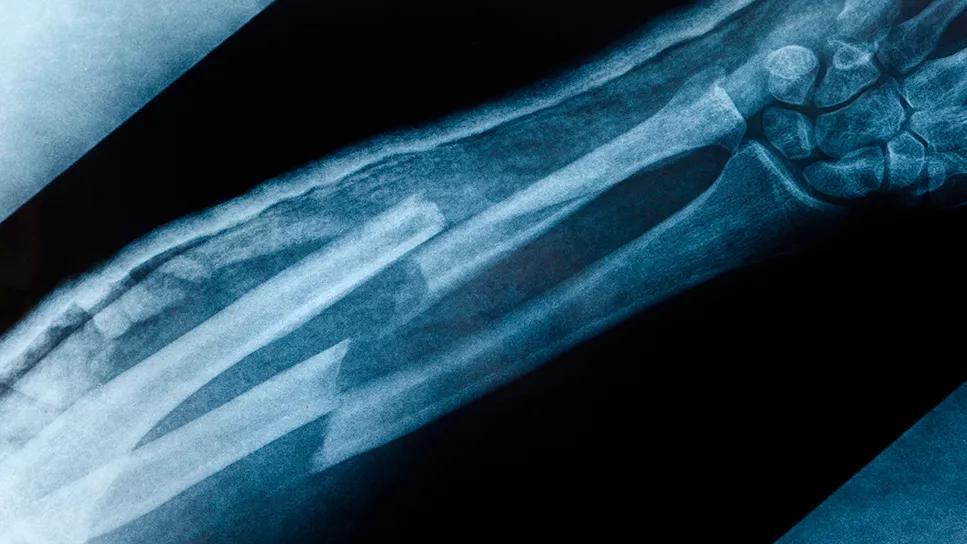

x-ray of bone fracture in a forearm

The most common fracture sites were the ribs, wrist and ankle. Over 80% of the fractures occurred with trauma, most often due to falls. The fracture types and anatomical locations were typical of osteoporotic fractures seen in older men.